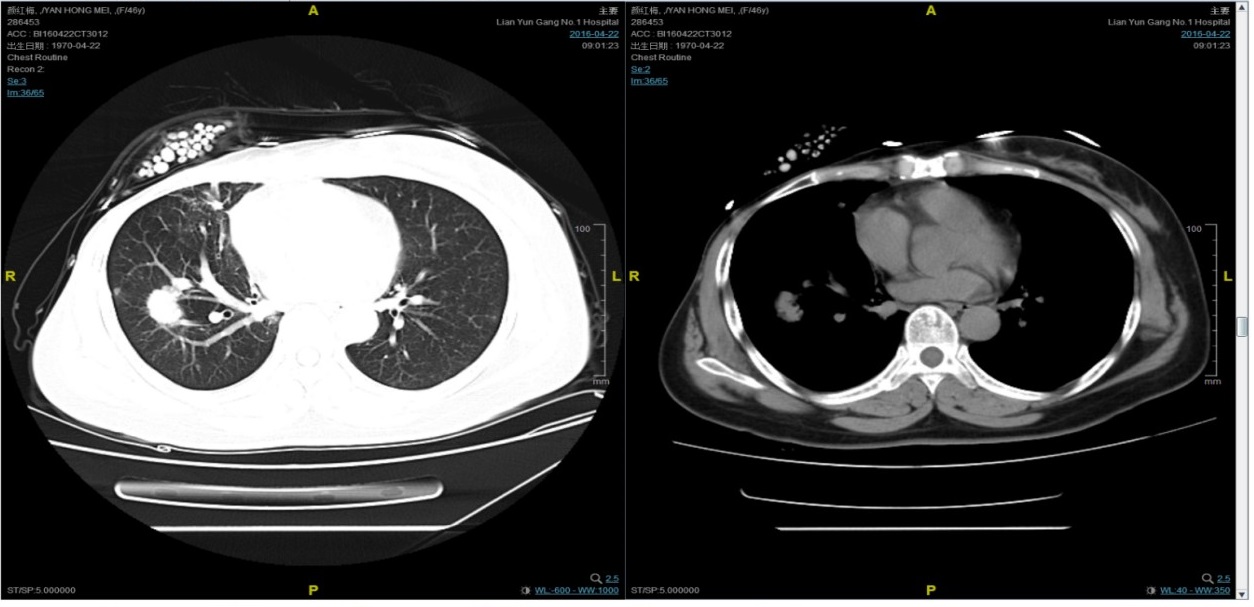

期间2016-4-22复查CT如下:

2016-7-5化疗结束后复查CT,疗效评价稳定。